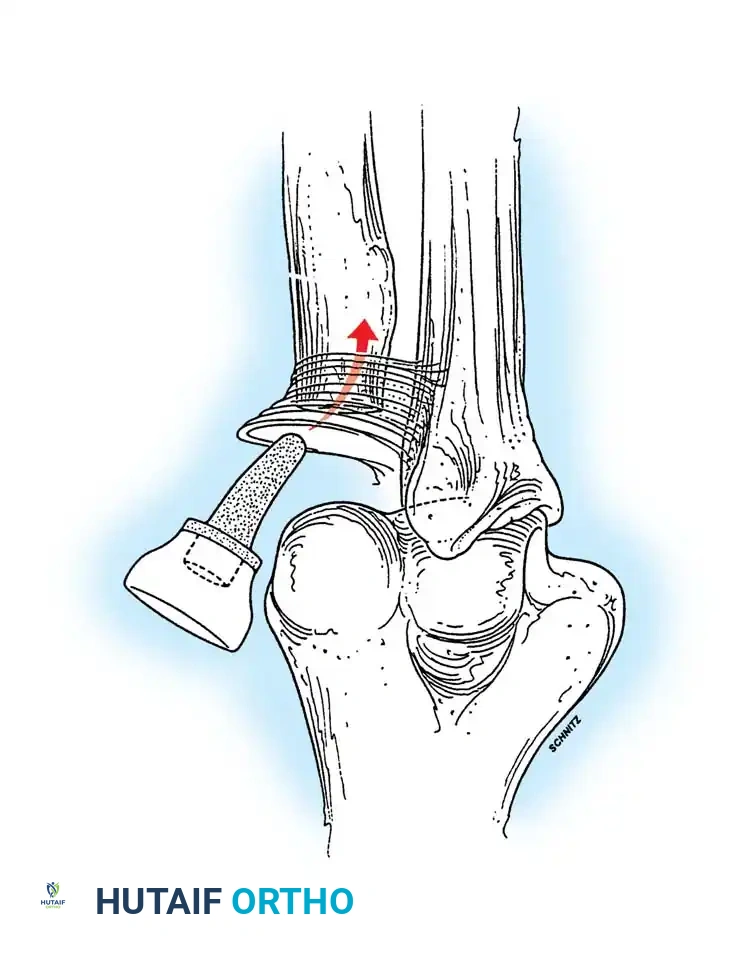

* Triceps-Reflecting (Bryan-Morrey): The triceps is reflected from medial to lateral in continuity with the anconeus and forearm fascia.

Associated Surgical & Radiographic Imaging